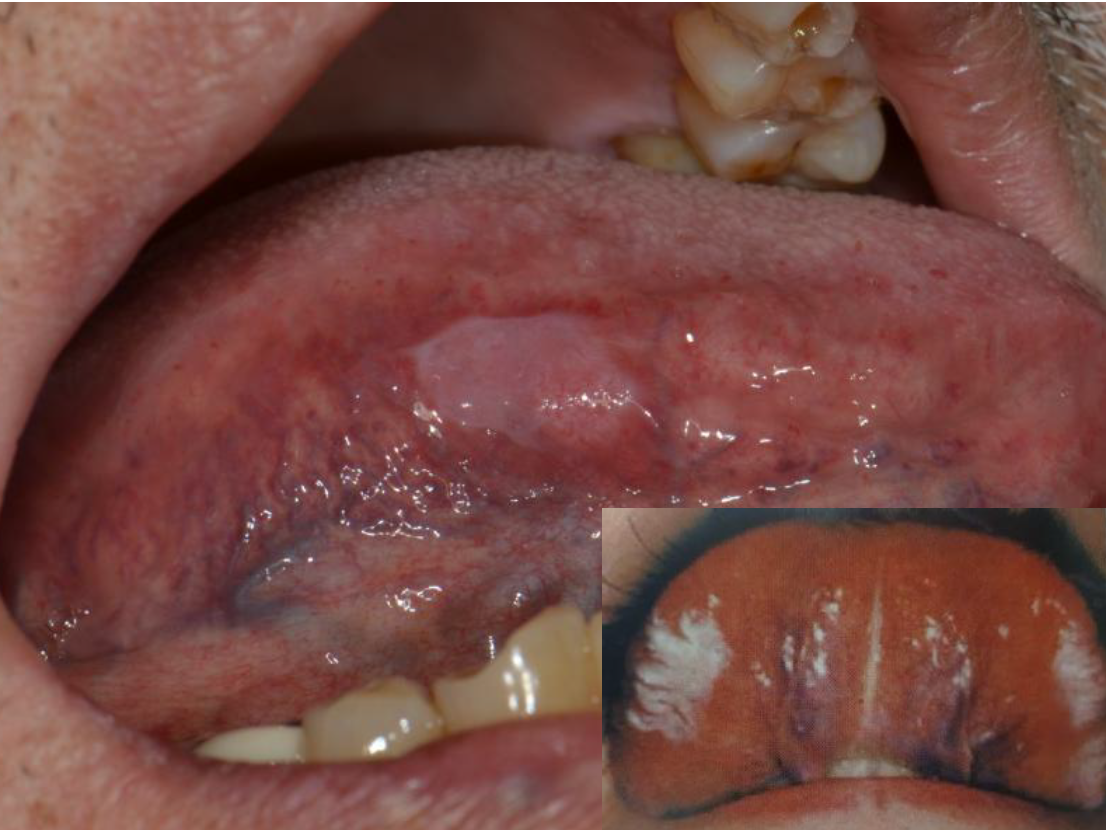

(20대는 젊어보이고 싶어서 그냥 끼워넣기) 조금 기분 나빠지는 사진이 있을 수 있으니 비위가 약한 분들은 사진은 통과해주세요 우선 구강암 증상부터 간단히 말씀드리고 제 이야기를 공유해보겠습니다! [구강암 증상]

1.3주 이상 회복되지 않아 심해지는 구내궤양 2. 염증 양상이 없어지지 않고 울퉁불퉁한 표면의 희고 붉은 병변 또는 검게 변색된 흑색종 3. 입안 혹의 크기가 커지고 뺨이 두꺼워지는 경우 4. 정상이었던 치아가 갑자기 심하게 흔들리거나 빠지는 경우 5. 구강 내 보철물이나 씹은 상처가 시간이 지나도 낫지 않는 경우

(실제 나의 뺨 점막 사진입니다)2. 염증의 양상이 없어지지 않고 뺨 점막 붉은 병변 및 아픈 통증 5. 교정 보철물 및 물고 온 상처가 시간이 지나도 없어지지 않을 경우 나는 2009년경에 치아 교정을 시작한 2011~2012년경 교정이 끝났어요 교정 치료를 하며 교정기 보철물로 뺨 점막이 더 많이 찔리고 긁히거나 하는 경우가 발생할 거요 정확하게 언제부터 적체증과 아픈 통증이 시작됐는지는 기억 나지 않지만 교정 치료가 끝난 후 시간이 지나고 식사를 하고 있고 오른쪽 뺨 점막 같은 곳을 강하게 몇번 씹은 기억은 있습니다. 붉은 병변과 아픈 통증을 내가 알고부터 5년 이내입니다 엄청 오래 된군요(?) 이렇게 하면 나도 구강 암 증상을 보면서 더욱 걱정이 되어 맞게 되었습니다 그래서 내가 2017년 동네 이비인후과 가장,2019년 동네 치과 방문 2020년 12월 직장 인근 여의도 치과 스케일링 겸 방문, 그리고 최근 2021년 2월 여의도 외의 치과 방문 등 4곳의 다른 병원에 가 봤어요 그 전에 붉은 병변과 아픈 통증은 계속되어 너무 걱정에서 최근 암 카페 현직 구강암 의사 분에 메모로 사진을 보내고 증세와 함께 들어 보았습니다 그 의사는 일반적인 염증의 양상과는 달리 보이기에 대학 병원의 조직 검사를 받도록 권하고 주신 당연히 그 의사는 직접 본 것이 없는 나의 증세와 사진상으로만 보던 거니까 정확한 진료를 받지 못하는 부분임을 참고하세요